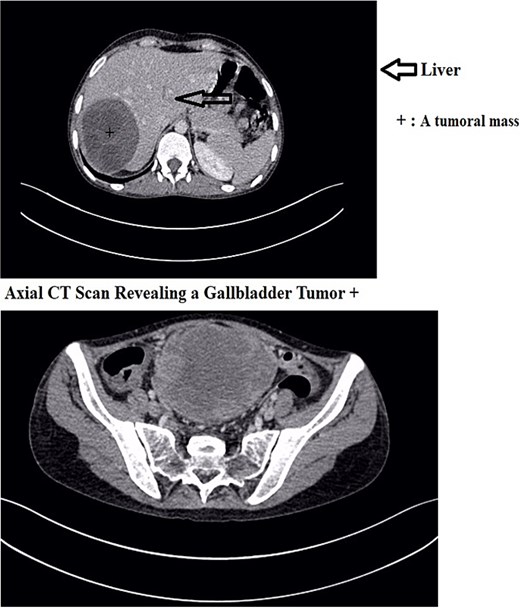

A 30-year-old woman, gravida 2 para 2, presented with a 10-day history of right upper quadrant (RUQ) abdominal pain. She had no significant medical or surgical history and denied systemic symptoms such as fever, weight loss, or fatigue. On examination, she was afebrile and hemodynamically stable, with a WHO performance status of 1. Abdominal palpation revealed localized tenderness in the RUQ. Laboratory investigations revealed mild leukocytosis (12 250/μL), Hb:10.8 g/dL, Plt:538000, TP:64%, Na:132 mmol/L, K:4.1 mmol/L, CRP:299 mg/L. Liver function tests showed GGT:36 U/L, PAL:46 U/L, ASAT:13 U/L, ALAT:6 U/L, total bilirubin:5 mg/L, direct bilirubin:3 mg/L. Urea and creatinine were 0.2 and 3.6, respectively. Contrast-enhanced CT revealed a large mass in the gallbladder bed, suspected to be a tubulo-papillary intracholecystic neoplasm (ICPN) (Figs 1 and 2), with an associated angiomatous liver lesion in segment III, hydatid cysts, and mild ascites. Exploratory laparotomy was performed, revealing a ruptured gallbladder tumor with extension into adjacent liver tissue and abdominal wall, and free biliary stones within the peritoneal cavity (Fig. 3).

Axial CT scan revealing a gallbladder tumor with invasion of adjacent structures.